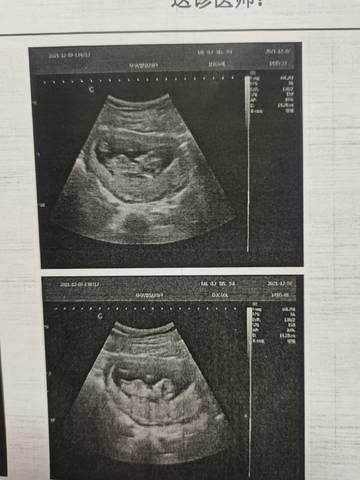

NT一次过了,第一次怀孕。好奇男宝宝还是小棉袄,有明白的能帮忙看看嘛胎心160 NT0.2

journal_insert_pic_1675676350journal_insert_pic_1675676378

你好。我们是判断不了男宝宝跟女宝宝的,孕期定期检查,我觉得宝宝健康就好的。祝心想事成 。

你好,通过这个来判断不太准确,不管是男宝宝还是女宝宝,都是妈妈的小惊喜,祝你心想事成。